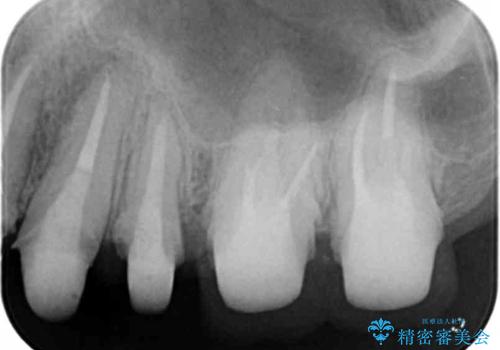

- 「虫歯が多発し、治療が終わらない。歯も無くなったし今後悪くならないような治療をしたい。」と精密治療を希望され来院されました。

虫歯の徹底的な除去やセラミック補綴、精密根管治療、歯周外科を行うことで、治療後に歯磨きがしやすく、かみやすい機能的な仕上がりへと導きます。

歯周外科手術をおこなったことでフェルールも獲得でき、破折リスクをより抑えることにも成功しています。